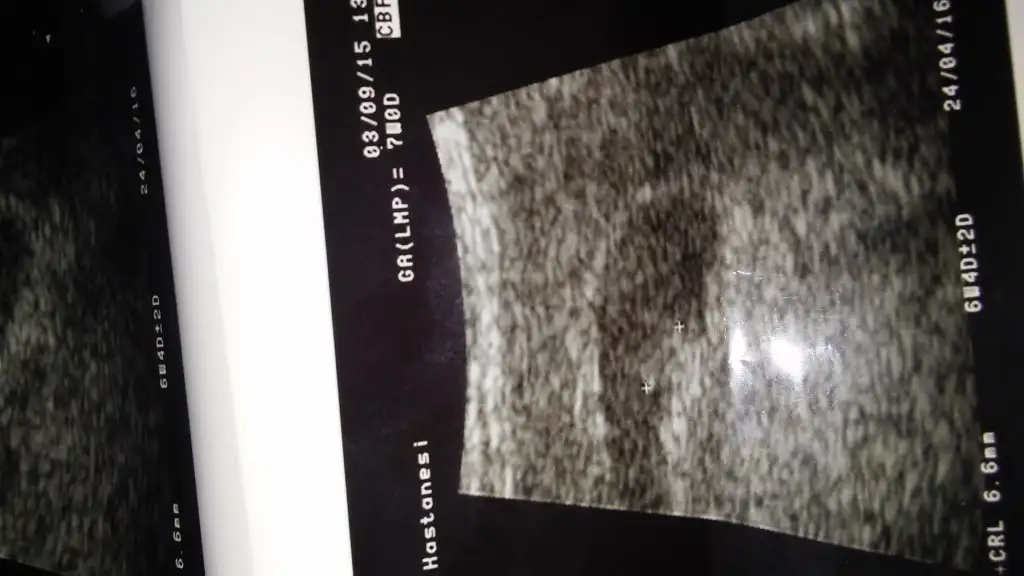

Arkadaşlar dün dr,a gittim... Doçent diye araştırma hastanesinde 1 buçuk yıldır ki kısaca hikayemi anlattım,,, gebelik istiyorum fakat 3 de düşüğüm oldu dedim. Çocuğun varmı deyince bende 3 tane var dedim. Hadsiz dr byn benimle alay etti, niye istiyorsunki 3 tane varmış dedi. Alay etti. Evet çok istiyorum dedim. İlk çocukmuş gibi istiyorum dedim. Ve sustu..aslında belki eşime ve bana takviye tavsiye eder diye gittim fakat bana folbiol iç dedi sadece.. Başka bir şeyede gerek yok dedi ve yaş faktöründen dolayı tembellik zayıflık olabilir dedi.. . Bana endokrine gitmemi önerdi şekerim hep sınır olurdu... Ondan şüphelendi, arkadaşlar bir de eşimde hipoglisemi rahatsızlığı var( düşen şeker). Gerçi ayarlayıcı hap İçmesi gerek fakat eşim içmiyor hap içmeyi hiç sevmez tatlı yiyecekler le kendine ayar çekiyor dicem oki. Onunda bu rahatsızlığı sperm kalitesini düşürüyor olabilirmi, çünkü geçen ay döllenme oldu kalitesiz olduğu için rahme tutunamamıştı,,, bir önceki tutunmuştu kalbi atmamıştı daha öncekide hep lekelenme oluyordu zaten 16 haftalık düşük olmuştu... Rabbim acaba 4. Yavruyu bana yazmamışmı kimbilir. Hakkımda hayırlısı olsun.